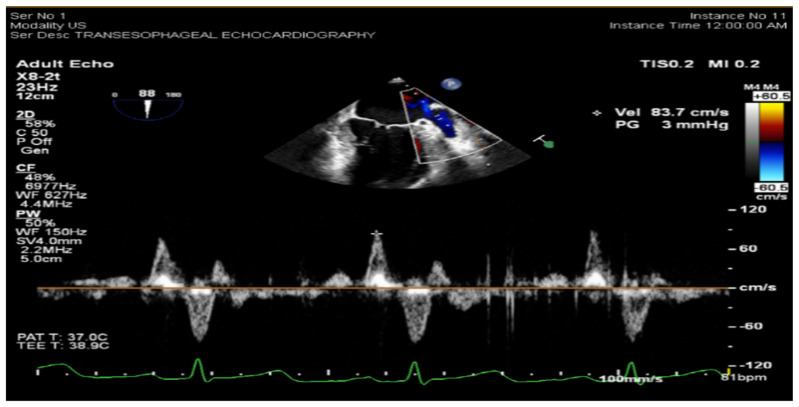

Methods: A prospective cohort of 32 patients with paroxysmal AF and structurally normal hearts, underwent either cryo- or radiofrequency ablation at a single tertiary center. Pre-ablation evaluations included LAS analysis via transthoracic echocardiography and LAAeV measurement via transesophageal echocardiography. Patients were followed for up to one year post-ablation, with recurrence defined as AF episodes lasting >30 seconds beyond a three-month blanking period. Statistical analyses assessed the predictive value of LAS and LAAeV, individually and in combination.

Results: AF recurrence occurred in 21.9 % of the cohort. Pre-ablation left atrial strain (LAS) values (global LAS ≥33.56 %, sensitivity 85.7 %, specificity 70 %, AUC = 81.4 %, P < 0.05) and left atrial appendage emptying velocity (LAAeV) (≥42.7 cm/s, sensitivity: 100 %, specificity: 87 %, AUC = 94 %, P < 0.001) were significantly associated with freedom from recurrence. The combination of LAS and LAAeV improved predictive accuracy to 100 % sensitivity and 94 % specificity (P value < 0.001). Post-ablation LAS showed inconsistent predictive value, with only apical-2 chamber global LAS achieving statistical significance (P = 0.002). Functional recovery of the left atrium post-ablation was minimal, suggesting limited reversibility of atrial remodeling.